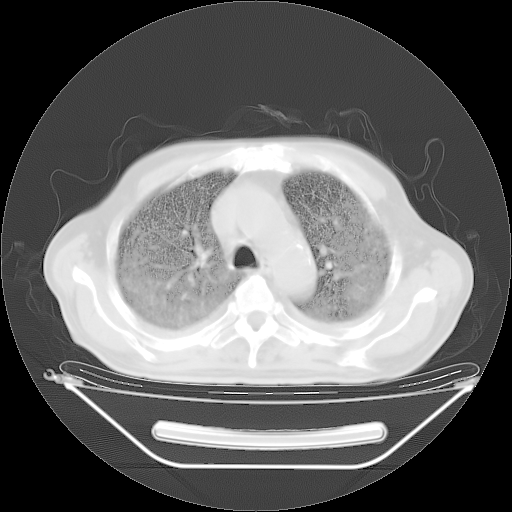

今天复查肺部CT,发现双肺广泛磨玻璃样改变。所以我把3月19日和5月9日相隔50天的肺部CT上传。请大家会诊。

5月9日肺部CT(在4月27日齐鲁医院肺部CT描述部分肺组织磨玻璃样改变,12天后肺组织广泛磨玻璃样改变)

2009年5月9日肺部CT

大致读了系列胸部CT:纵隔窗无明显异常,肺窗:从4、27至今:主要是双肺中下野外带可见毛玻璃样改变,目前处于急性肺泡炎阶段,至于原因考虑1、结替组织或胶原血管性疾病所致?2、恶性疾病如恶组在肺部所致的表现或细支气管肺泡癌?3、药物或其它原因如肺蛋白沉着症所致肺泡炎目前不太可能?总之,明天就去请我院的呼吸科、感染科、血液科和临免专家会诊哈。